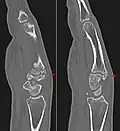

Additional images

Carpal boss in CT.